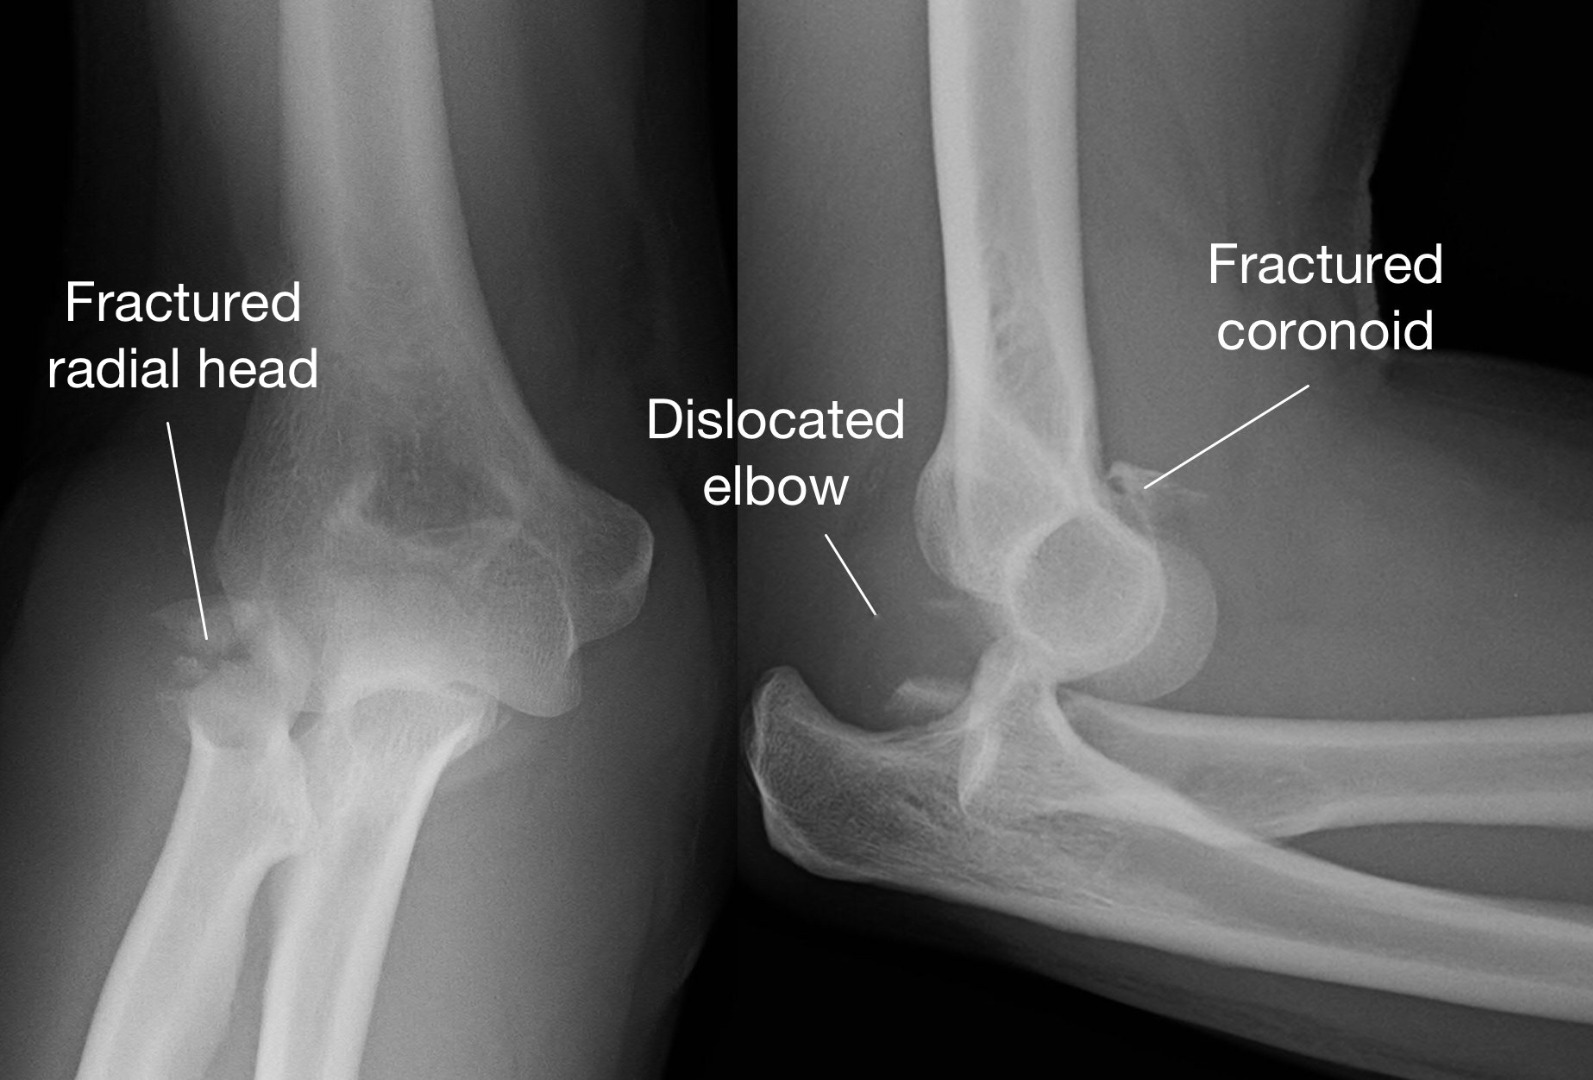

• X-rays: The gold standard for identifying the location and type of bone breakage.

• CT Scans: Used when more detail is needed, such as in complex joint injuries.